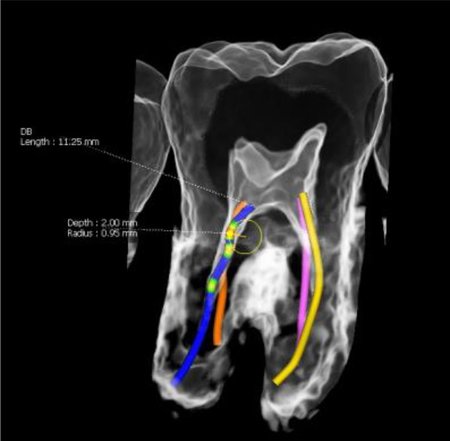

Höchste Detailschärfe

Das Green X ist mit 49μm bei einem FOV von 4x4 cm das Gerät mit einem der weltweit höchsten Auflösungen und der daraus resultierenden Detailschärfe. Dank der byzzEz3D-i Software mit dem Endo-Modul rekonstruiert diese aus ultrahochauflösenden Schichtaufnahmen perfekte 3D Aufnahmen. Diese können dann als Hologramm in allen drei Dimensionen vermessen werden.

Ein ideales Instrument zur Vorbereitung für jede Wurzelkanalaufbereitung und WSR und auch ein hervorragendes Hilfsmittel zur 3D-Visualisierung, Behandlungsplanung und Patientenberatung.

Die byzzEz3D-i Software mit dem erweiterbaren Endo-Modul rekonstruiert aus den ultra-hochauflösenden Schichtaufnahmen perfekte 3D-Aufnahmen. Die 3D-Endo-Aufnahmen können als Hologramm in allen drei Dimensionen vermessen werden. Sowohl die Bi- und Trifurkation, Kanalanzahl, Kanalverlauf, Kanallänge und -durchmesser sowie die Krümmungsradien können einfach farblich gekennzeichnet werden. Damit ist das 3D-Endo-Modul nicht nur ein ideales Instrument zur Vorbereitung für die Wurzelkanalaufbereitung und WSR, sondern auch ein hervorragendes Hilfsmittel zur 3D-Visualisierung, Behandlungsplanung und Patientenberatung.

Green X von orangedental Endo Aufnahme